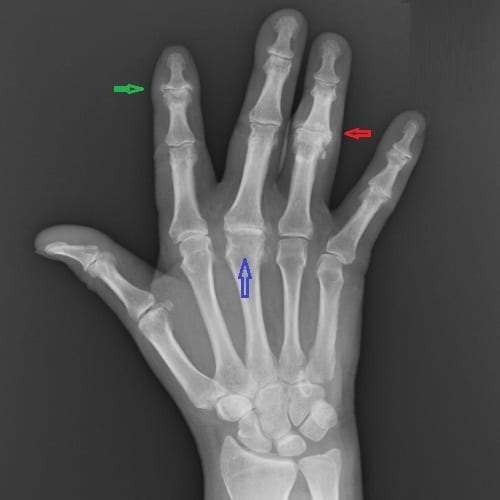

- Обзорная рентгенограмма, так как симптомы данного характера являются характерными для ревматоидного артрита.

Так выглядит ревматоидный полиартрит, не запускайте болезнь до такого, лечитесь!

- Рентгенография. На ранних стадиях ревматоидного артрита у человека могут появится только припухлости мягких тканей, которые не обнаруживаются на рентгеновском снимке, поэтому при ранней диагностики к рентгенографии прибегают редко. Рентген обычно используют, когда болезнь прогрессирует. Рентген может помочь обнаружить повреждение костей (эрозии), возникающие в результате длительного/продолжительного ревматоидного артрита. Он также может обнаружить сужение пространства суставов, возникших при деградации хряща и сближении кости с суставом.

Рентгенография суставов

Рентгенографическое исследование необходимо как для постановки диагноза, так и для наблюдения, а также оценки развития заболевания в динамике.

Основными симптомами рентгенологических изменений со стороны суставов являются:

- околосуставной остеопороз (патологическое снижение плотности) верхнего и нижнего края кости – эпифиза;

- сужение щели сустава и начинающееся развитие краевых изъязвлений (узур);

- Разросшаяся деформированная суставная оболочка становится рыхлой, «наползает» на хрящ, срастаясь с ним, и разрушает его. Такое образование называется паннусом.

Кроме рентгена, очень желательными являются денситометрия и сцинтиграфия в динамике именно мелких суставов с захватом лучезапястных и голеностопных суставов и скрупулезным подсчетом эрозий.

Прогрессирование ревматоидного полиартрита приводит к развитию анкилозов (неподвижности сустава). Особенно рано они развиваются в мелких суставах запястья, срастающихся в единый костный блок.